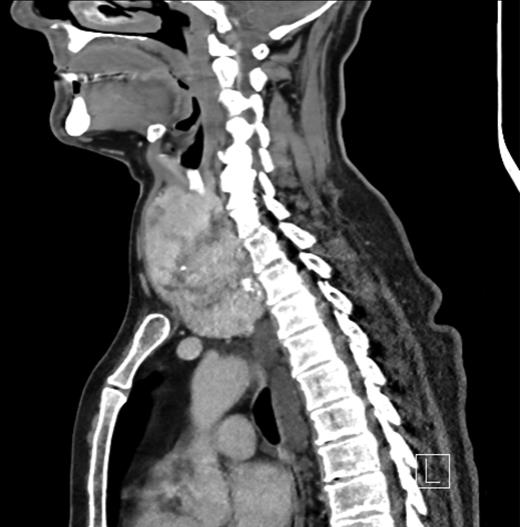

Thyroid function tests were normal. He underwent a computed tomographic (CT) scan of the neck and chest (Figs 1–3). It showed a large multinodular goitre with retrosternal extension of the left lobe to the arch of the aorta. The trachea was deviated to the right. Paraoesophageal swellings were noted in the upper posterior mediastinum, the largest of which measured 2 cm. These were non-enhancing masses, with no evidence of haemorrhage. The case was reviewed in a multidisciplinary meeting to exclude the differential diagnosis of necrotic paraoesphageal lymph nodes. The oesophagus was unremarkable, with no thickening or air-fluid level. In view of this and the continuity of the swellings with the thoracic duct, no further investigation or biopsy was undertaken.

Sagittal CT image showing a thyroid goitre with retrosternal extension and paraoesophageal swellings.